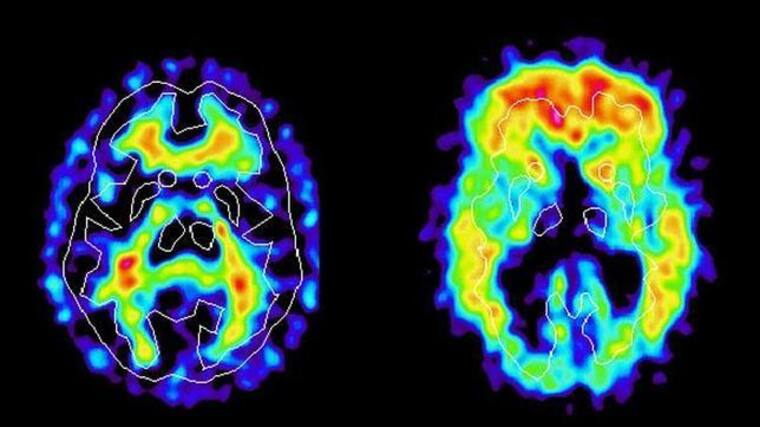

El Alzheimer es una enfermedad neurodegenerativa que afecta principalmente a las personas mayores. Es la forma más común de demencia y se caracteriza por un deterioro progresivo de las funciones cognitivas, como la memoria, el pensamiento y el comportamiento.

El Alzheimer ocurre debido a la acumulación anormal de proteínas en el cerebro, lo que daña y destruye las neuronas. Aunque no tiene cura actualmente, hay tratamientos y terapias que pueden ayudar a manejar los síntomas y mejorar la calidad de vida.